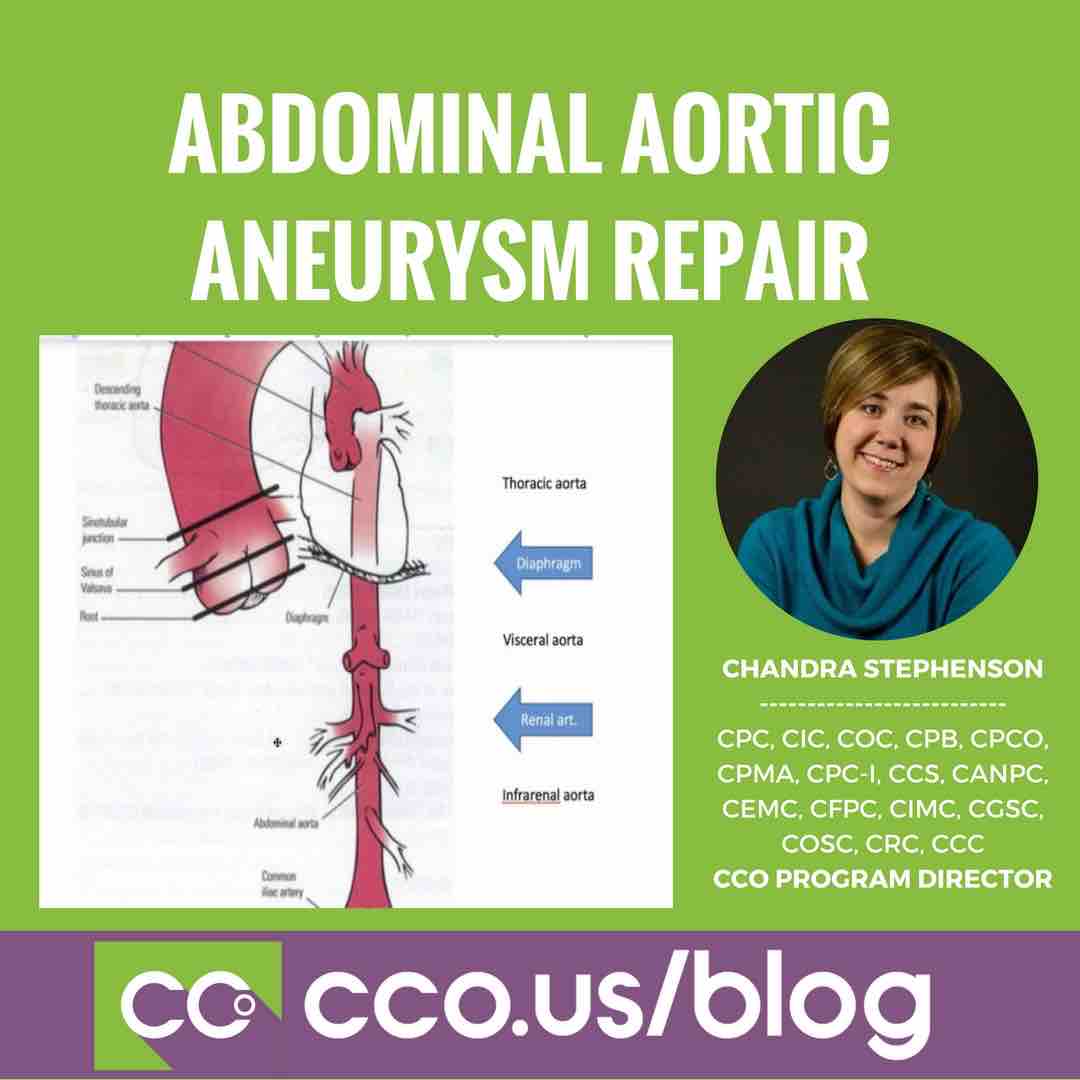

The most common location of arterial aneurysm formation is the abdominal aorta, specifically, the segment of the abdominal aorta below the kidneys. An abdominal aneurysm located below the kidneys is called an infrarenal aneurysm. An aneurysm can be characterized by its location, shape, and cause.

Aneurysms can develop anywhere along the aorta, but most aortic aneurysms occur in the part of the aorta that's in the belly area (abdomen). Several things can play a role in the development of an abdominal aortic aneurysm, including: Hardening of the arteries (atherosclerosis).

Most aneurysms are in the aorta, the main artery that runs from the heart through the chest and abdomen. There are two types of aortic aneurysm: Thoracic aortic aneurysms (TAA) - these occur in the part of the aorta running through the chest. Abdominal aortic aneurysms (AAA) - these occur in the part of the aorta running through the abdomen. ...